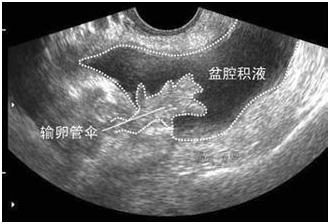

2、异位妊娠,多有不规则阴道出血、下腹痛、月经推迟等症状,尿妊娠试验阳性。

受精卵在子宫体腔以外着床的现象称为异位妊娠,最常见的是输卵管妊娠。当输卵管妊娠流产或破裂,就会输卵管壁破裂出血,血液聚积在子宫直肠陷凹,进而形成盆腔积液。从后穹窿可以抽吸出不凝固血液。